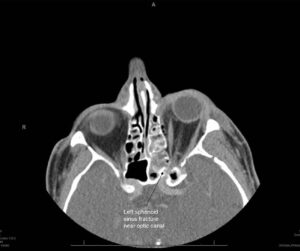

Left sphenoid sinus fracture near optic canal

TRAUMATIC OPTIC NEUROPATHY

The optic nerve runs from the back of the eye to the brain, where images from the eye are processed and interpreted. Some people who sustain a head injury damage their optic nerve. This can be due to fractures of the bony canal that the nerve runs through or from swelling or damage to the blood vessels supplying the optic nerve. Traumatic optic neuropathy causes loss of vision in the affected eye. Emergency Trauma services in Mumbai are available at Wavikar Eye Hospital.

The loss of vision is usually instantaneous. A full eye examination is performed to assure no damage has occurred to the eye itself, as well as a CT scan or MRI scan to assess the optic nerve and nerve canal.